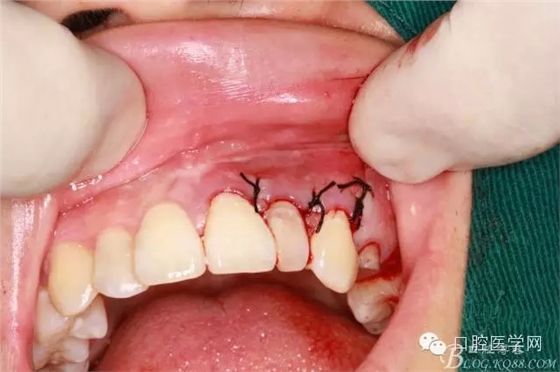

填明膠海棉(建議植骨和應(yīng)用生物膜)患者不同意因費(fèi)用較高

復(fù)位縫合

填塞牙周塞治劑